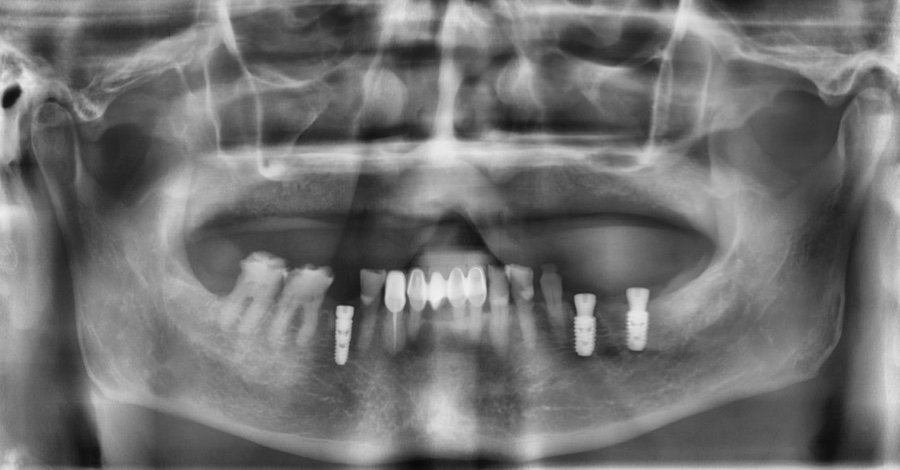

치료 전,후 사진 / 2024. 12. 18~2025.06.19

*치료 기간 : 2024. 12. 18~2025.06.19